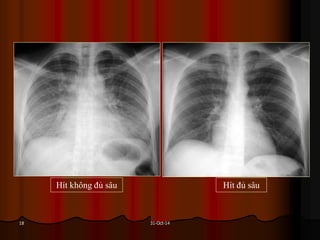

Được xem là hít đủ sâu khi ta thấy được hình chiếu của xương

sườn lên phổi 6 cung sườn trước hoặc 10 cung sườn sau.

Hít không đủ sâu Hít đủ sâu